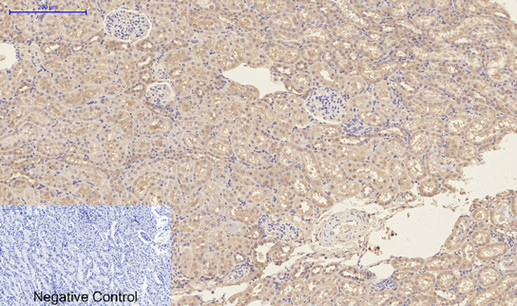

- Immunohistochemistry analysis of paraffin-embedded rat kidney tissue using CD23 antibody.High-pressure and temperature Sodium Citrate pH 6.0 was used for antigen retrieval.Negative control was used by secondary antibody only.